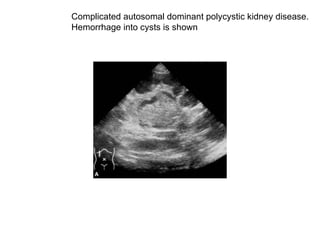

Complicated autosomal dominant polycystic kidney disease.  Hemorrhage into cysts is shown

Complicated autosomal dominant  polycystic kidney disease. (A and B)  Hemorrhage into cysts is shown